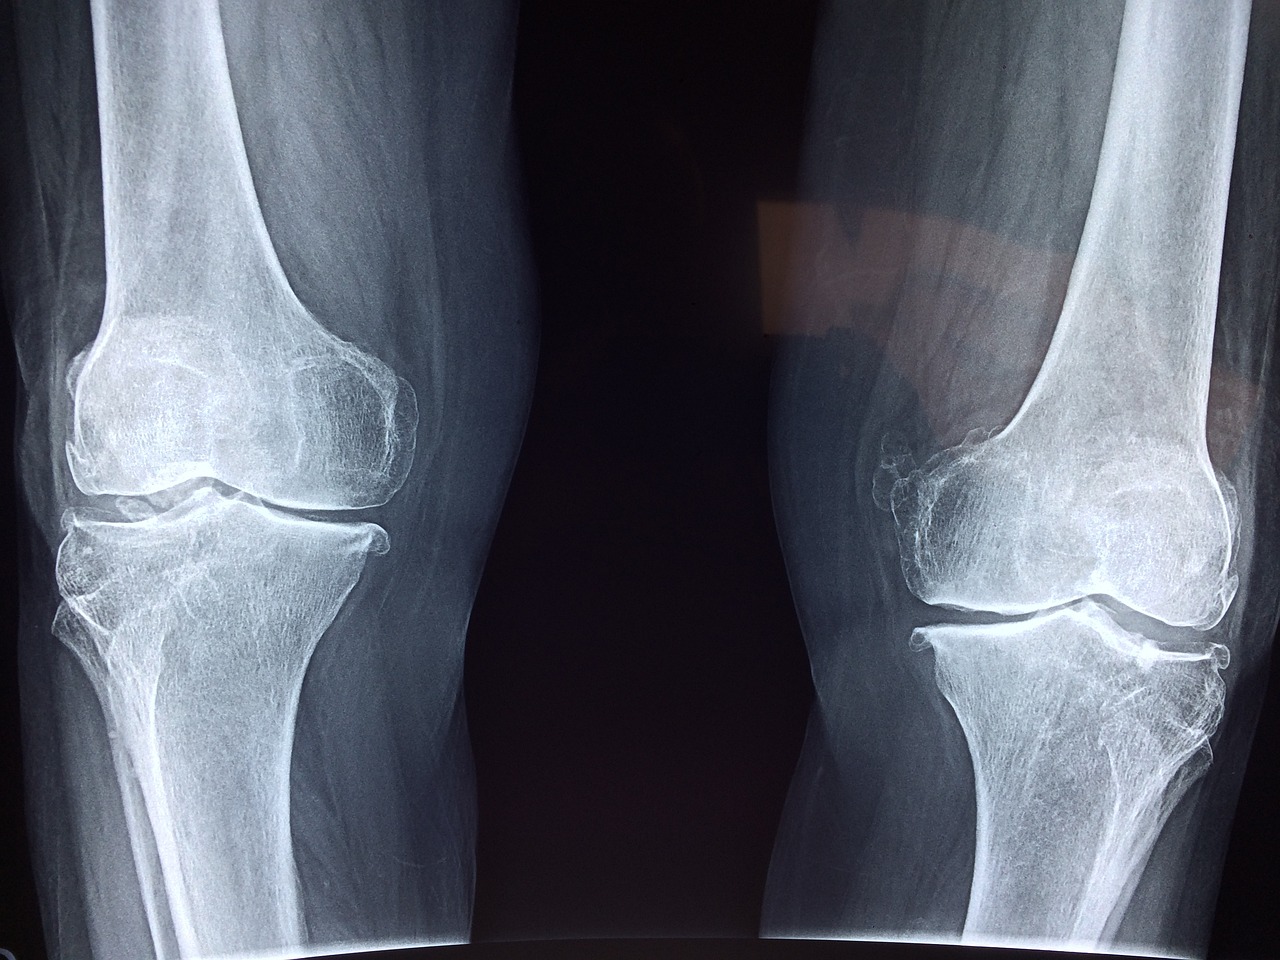

- 관절염: 골관절염이나 류마티스 관절염은 무릎 관절의 염증을 일으켜 체액 분비를 증가시키고, 오금 부위의 압박감 및 통증으로 나타날 수 있습니다.